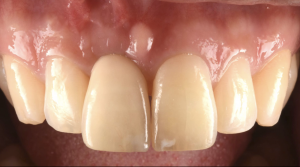

土台ごと折れた前歯をインプラントで治療した症例【前歯部審美症例12】

初診時。前歯がグラつくとのことでご来院されました。詳しく調べてみると、かぶせと土台が根っこごと折れてしまっている状態でした。非常に太い土台が入っていたことにより、根が折れやすい状態だったと予想できます…